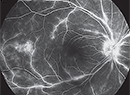

HORV: A Rare But Devastating Complication of Endophthalmitis Prophylaxis

Hemorrhagic occlusive retinal vasculitis has been associated with routine intracameral vancomycin use.